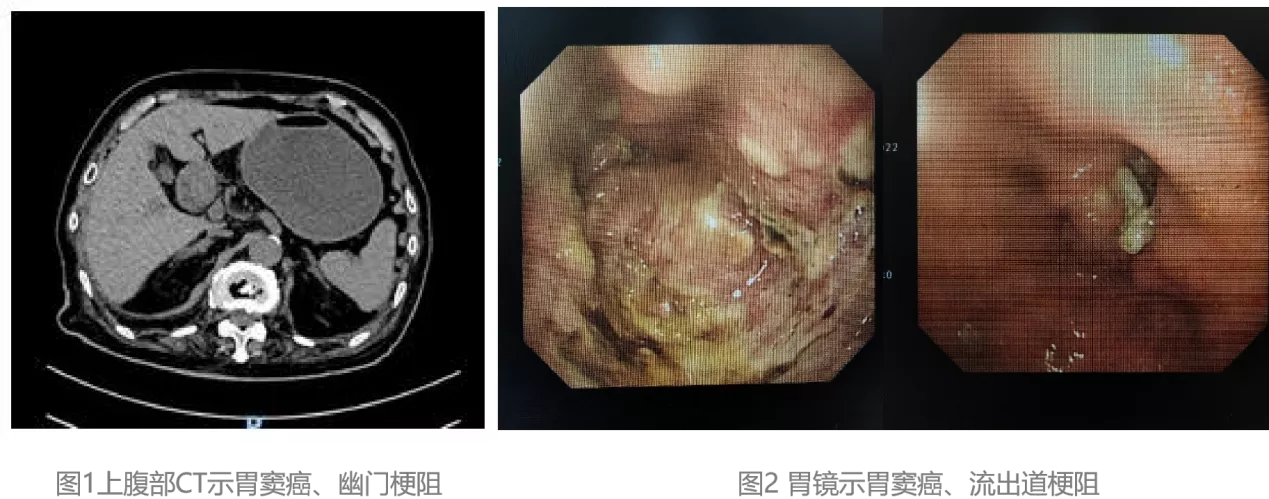

腹部CT示:幽门梗阻、胃潴留(图1)。胃镜示:胃窦癌、流出道梗阻(图2)图片

综合患者临床症状呕吐,隔夜食物,辅助检查示幽门梗阻征象,最终确诊为幽门梗阻。